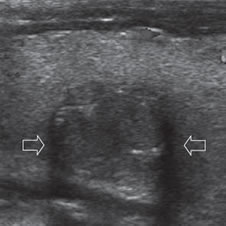

Un nódulo que tiene un componente quístico significativo, usualmente es un nódulo benigno hiperplástico, que ha acumulado abundante coloide (Figura 2a) o bien, un nódulo sólido que ha experimentado un proceso de degeneración colicuativa o hemorragia (Figura 2b). El coloide o el contenido líquido de un nódulo se ve anecogénico (negro en la imagen ecográfica) y las estructuras sólidas se ven ecogénicas (distintos tonos de grises), siendo la ecogenicidad similar al del parénquima tiroideo. En un nódulo sólido la ecoestructura y la ecogenicidad pueden ser variables. En general, la frecuencia de carcinoma es muy baja en nódulos quísticos13 y la mayoría de los carcinomas se presentan como nódulos sólidos (Figura 2c).

Figura 2. a) Quiste coloideo anecogénico y focos ecogénicos (flecha) con artefacto en cola de cometa; b) Nódulo mixto sólido-quístico (cabezas de flechas). Imagen vegetante (flecha) adherida a un tabique que se proyecta al lumen; c) Comparación entre el aspecto ecográfico de un cáncer papilar sólido (flecha abierta) y un quiste coloideo anecogénico.